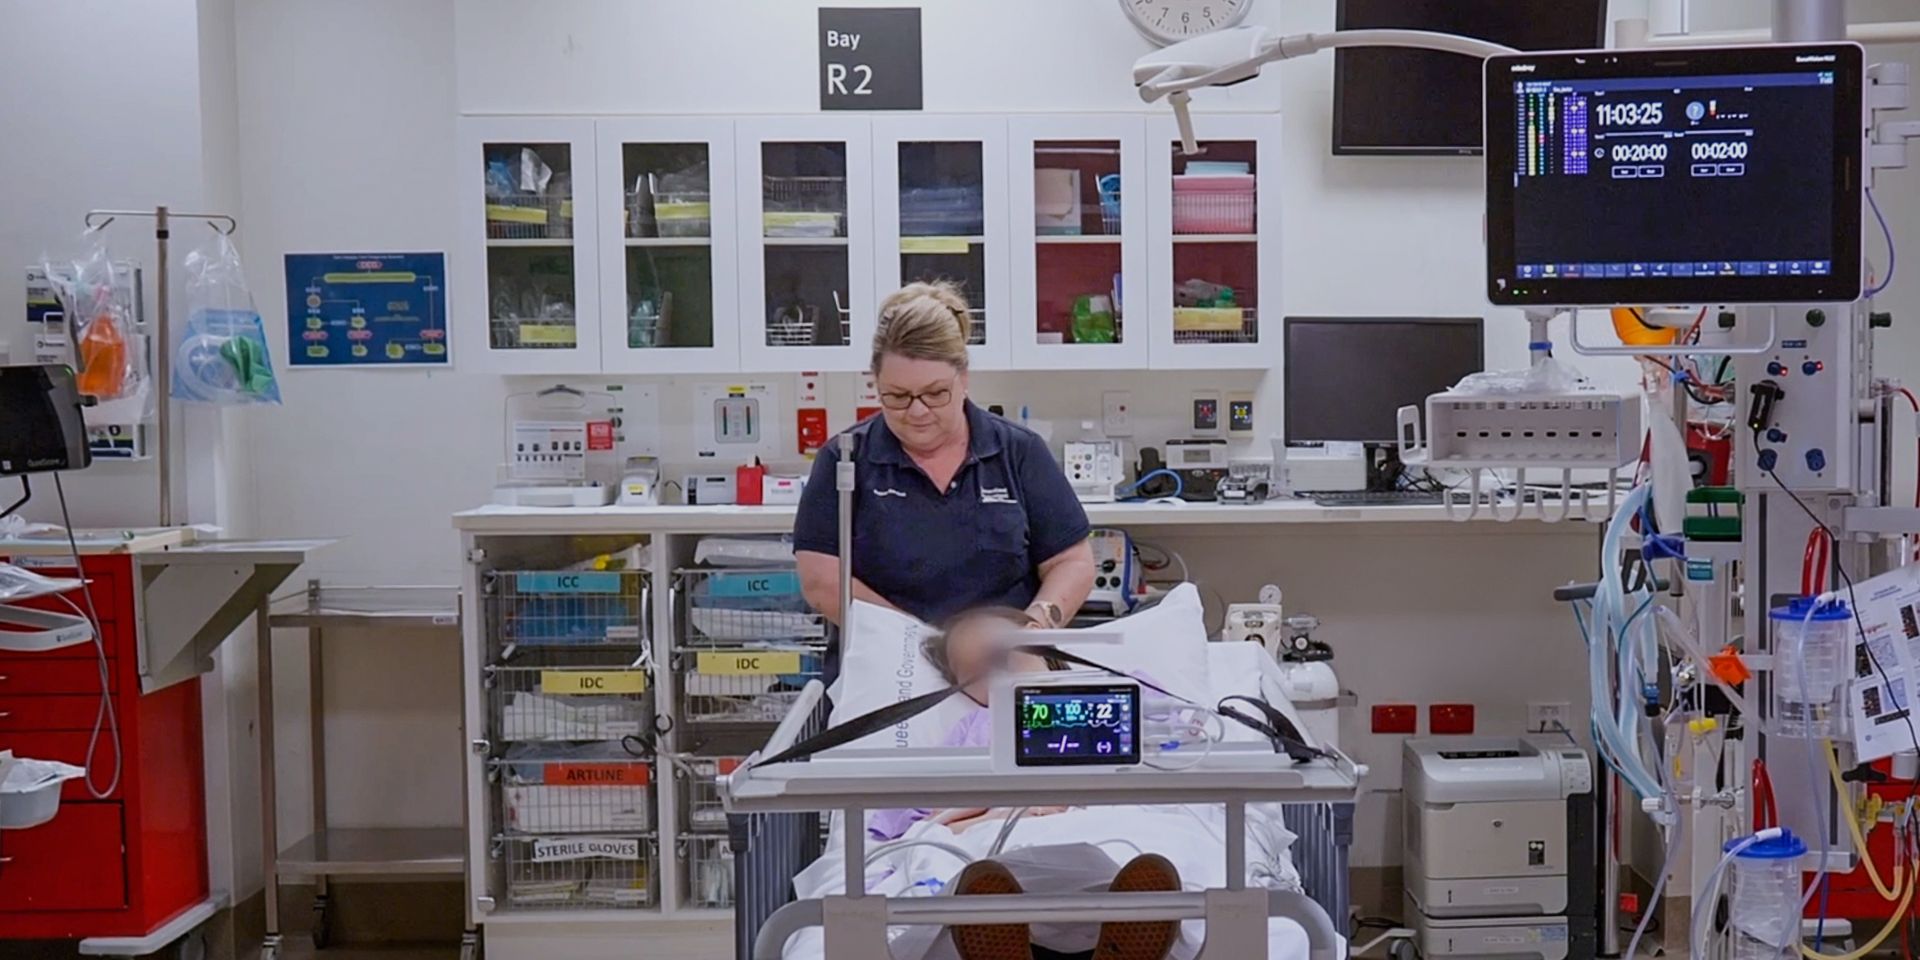

Customer Stories ’Į£ 2025-07-01

Sustainable Care Across Distances - Townsville's Journey with Mindray in Digital Transformation